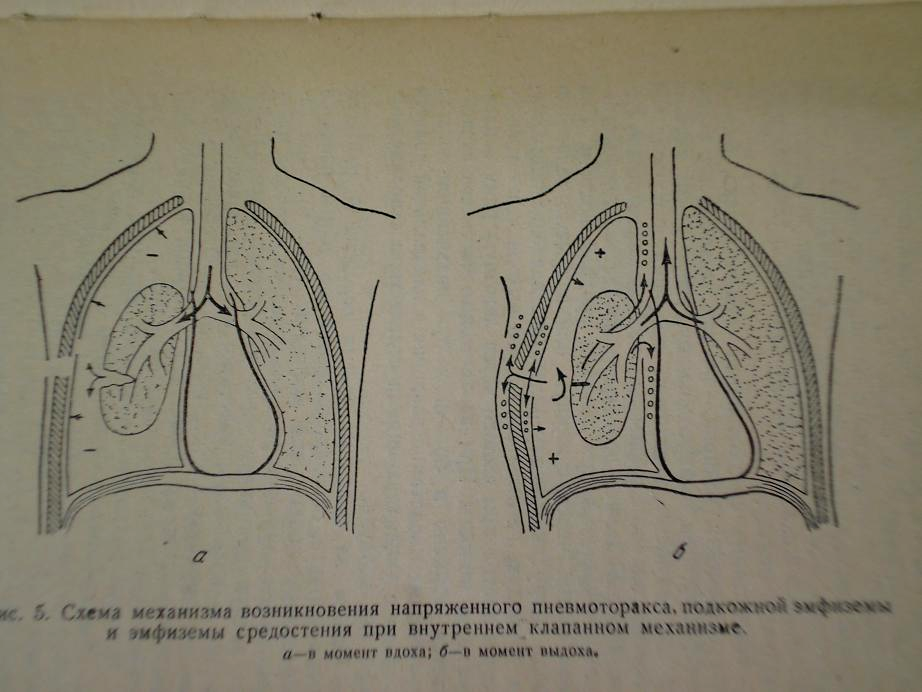

Схемы дыхания: Пневмоторакс на изображениях